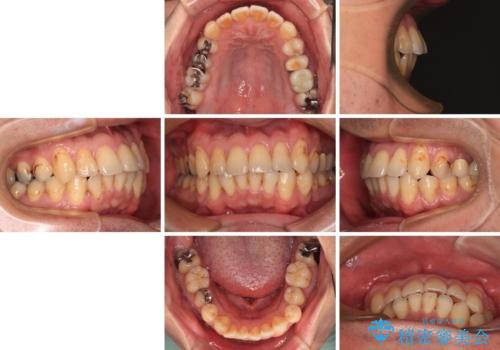

- 銀歯やむし歯でものが挟まるところが気になるとのことで来院された患者様です。

左上の奥歯は神経が失活しており、根管治療が必要な状態でした。

その他は銀歯のインレー(部分的な詰め物)が装着されており、それらはむし歯を除去した後にセラミックインレーにて修復治療を行い、左下と根管治療を行う左上の奥歯はオールセラミッククラウンにて補綴治療を行うこととしました。

根管治療の途中で、矯正治療の後戻りが気になるとのことで、下顎前歯の叢生を改善するためにマウスピース矯正を並行して行いました。